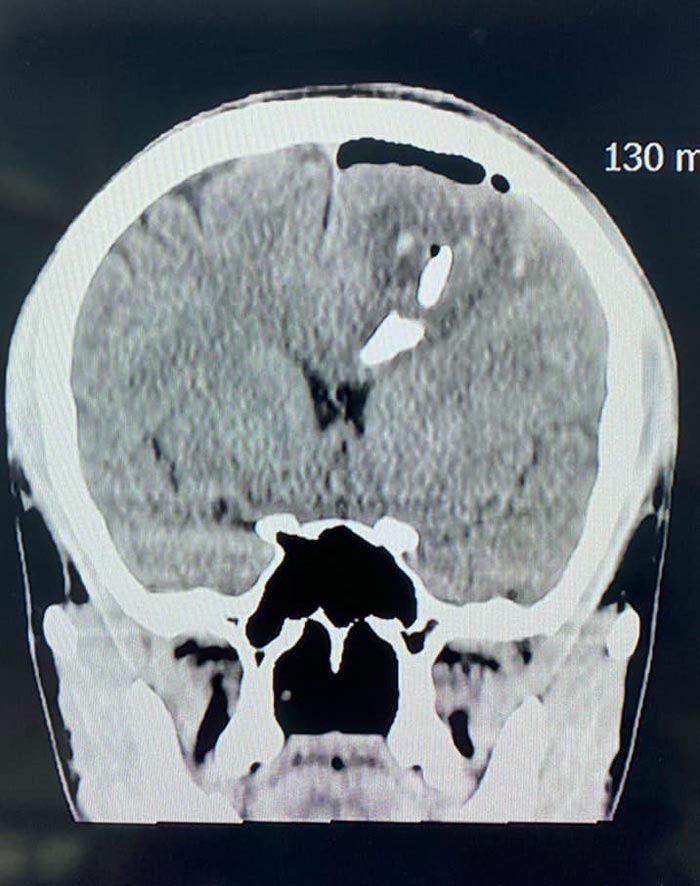

โดยเมื่อวันที่ 13 สิงหาคม 2566 นายแพทย์อารักษ์ วงศ์วรชาติ หรือ คุณหมออารักษ์ ผู้อำนวยการโรงพยาบาลประจวบคีรีขันธ์ ก็เป็นอีกหนึ่งคนที่ออกมาโพสต์เตือนเรื่องนี้ ระบุว่า "ขอให้ระมัดระวังอุบัติเหตุในช่วงสงกรานต์" พร้อมยกเคสตัวอย่างผู้ป่วยประสบอุบัติเหตุทางสมองอย่างรุนแรง กะโหลกศีรษะแตกเป็นชิ้น ๆ ฝังลึกเข้าไปในเนื้อสมอง ดังนี้

กรณีตัวอย่างผู้ป่วยประสบอุบัติเหตุ ทางสมองอย่างรุนแรง ทำให้กะโหลกศีรษะแตกเป็นชิ้น ๆ ฝังลึกเข้าไปในเนื้อสมอง ทำให้มีภาวะเลือดออกในสมอง และเนื้อสมองถูกทำลายไปบางส่วน ผู้ป่วยยังรู้สึกตัว ถูกนำส่งโรงพยาบาลประจวบคีรีขันธ์

หลังจากดูแลเบื้องต้น เอกซเรย์สมอง ปรึกษาแพทย์ผู้เชี่ยวชาญด้านศัลยศาสตร์สมองและระบบประสาท เตรียมตัวผู้ป่วย นำเข้าห้องผ่าตัดทันที

การผ่าตัดสมองค่อนข้างละเอียดอ่อน เพื่อหยุดเลือดที่ออก เอาเศษกระดูก กะโหลกศีรษะ ลิ่มเลือดที่ตกค้างออก เย็บปิดเยื่อหุ้มสมอง การผ่าตัดใช้เวลาประมาณ 1 ชั่วโมง ประสบผลสำเร็จเป็นอย่างดี ประเมินอาการทางสมองหลังผ่าตัดเป็นที่น่าพอใจ